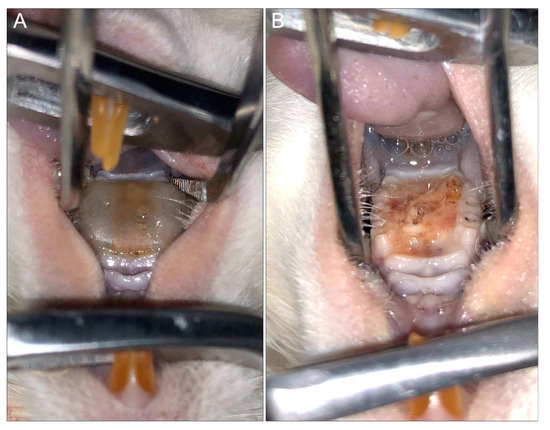

Another common disadvantage among the existing models is that devices are custom-designed for each animal, which requires making impressions of the palate for each individual rat. Furthermore, the devices are fabricated in a dental lab and may require adjustments to ensure adequate fit, a process that is costly and time-consuming. Most recently, Sultan et al. [76] developed a three-dimensional (3D) printed digitally designed rat intraoral device with precise universal fit based on a scan taken of only one rat palate. In addition to the universal fit, a unique advantage of the 3D-printing technology is the high throughput for fabricating devices and, importantly, if needed, modifications to the design can be digitally made rapidly (Figure 4).

Figure 4. Rat model of denture stomatitis. (A) Three-dimensional (3D)-printed denture with intimate fit to the hard palatal-mucosa of a rat. (B) Denture stomatitis in a rat model demonstrating profound edema and a thick yellow biofilm of the denture-bearing hard palatal mucosa (top: tongue; bottom: hard palate).

Several of the available rat models were adapted and used to evaluate therapeutic strategies targeting DS [63,76]. Whether involving topical or systemic administration of antifungal therapy, as expected, the models demonstrated that treatment is ineffective once mature biofilms are formed on the surface of implanted devices [63,76]. However, a recent study evaluating the efficacy of a novel antimicrobial peptide-based hydrogel formulation against OC and DS demonstrated the formulation to be efficacious in preventing disease development in a mouse model of OPC and in a rat DS model [76,219]. Combined, the findings from these studies clearly indicate the need for developing targeted preventative therapeutic strategies against biofilm-associated infections that tend to be recalcitrant to therapy, such as DS [40,233,234].